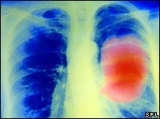

Prueban vacuna contra el cáncer

Una prueba clínica a gran escala para verificar la efectividad de una vacuna contra la forma más común de cáncer de pulmón comenzó esta semana.

Más de 1.300 pacientes en el mundo participarán en las pruebas del medicamento Stimuvax, que en los ensayos clínicos preliminares demostró aumentar la posibilidad de supervivencia en muchos enfermos.

La vacuna funciona estimulando al sistema inmunológico a que ataque a las células cancerosas. Fue creada para curar el cáncer de células no pequeñas (o no microcítico) que es la forma más común de la enfermedad en el Reino Unido.